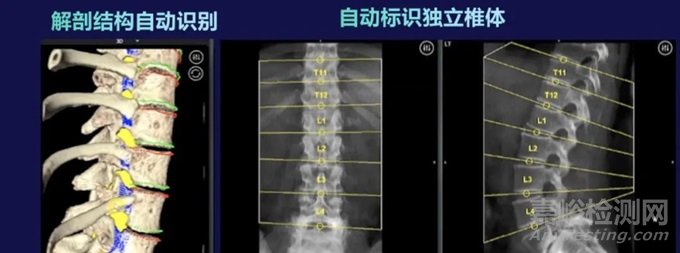

術(shù)前計(jì)劃使用患者的CT數(shù)據(jù),憑借Mazor X 的解剖洞察引擎,識(shí)別關(guān)鍵解剖結(jié)構(gòu),通過全局術(shù)前規(guī)劃軟件結(jié)合人工智能,輔助醫(yī)生進(jìn)行多種手術(shù)規(guī)劃,包括螺釘、皮膚切口、通道、融合器規(guī)劃,脊柱參數(shù)測(cè)算,畸形分型,截骨矯形模擬等,為患者制定進(jìn)行個(gè)性化、定制化的全局手術(shù)規(guī)劃。

術(shù)中配準(zhǔn):利用 Mazor X 獨(dú)有的單椎體跨模態(tài)配準(zhǔn)技術(shù),僅需兩張二維影像即可完成術(shù)前計(jì)劃與患者的配準(zhǔn)。

采用單椎體的跨模態(tài)配準(zhǔn)方式,比通過術(shù)中三維掃描配準(zhǔn)的傳統(tǒng)智能設(shè)備更高效,大幅減少輻射劑量并避免術(shù)中制定手術(shù)計(jì)劃而增加的額外時(shí)間。